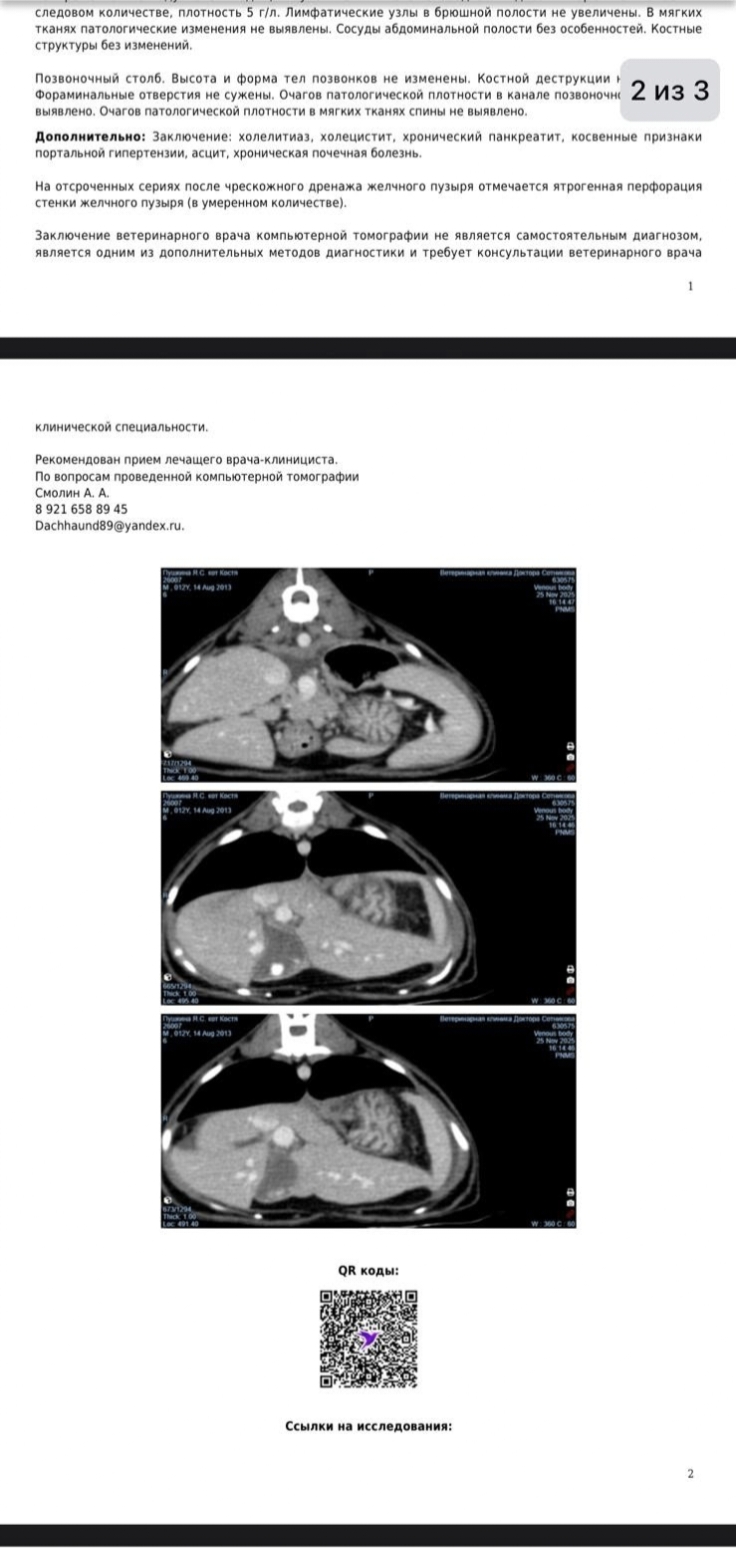

В нашем городе коту не смогли помочь, в операции отказали, слишком большие риски. Кота перевезли на лечение в Санкт-Петербург. Лечение уже встало более 200 000 рублей, а в ближайшие дни надо ещё не менее 100 000 рублей. Кот с 6200 похудел до 3700. Уже не кушает самостоятельно. Перед операцией ( 72 200 руб) требовалось переливание крови. Вчера, 29.11.25 начали переливать кровь ( оплатили 47000). Сегодня, 30.11, переливание закончено показатели крови улучшились , разрешено сделать операцию и установить эзофагостому ( 22100 руб.)